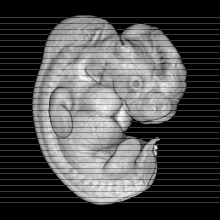

Carnegie Stage 17 (41 post-ovulatory days)

Most embryos at stage 17 are approximately 41 postovulatory days old and measure 11-14 mm in length. Distinguishing criteria for this stage include distinct digital rays in the hand plate, a rounded digital plate in the foot, a complete complement of hillocks on the mandibular and hyoid arches, distinct nasofrontal grooves, and a slight indication of a lumbar curvature.

This specimen does not represent normal development. The caudal nueral tube has failed to close properly.